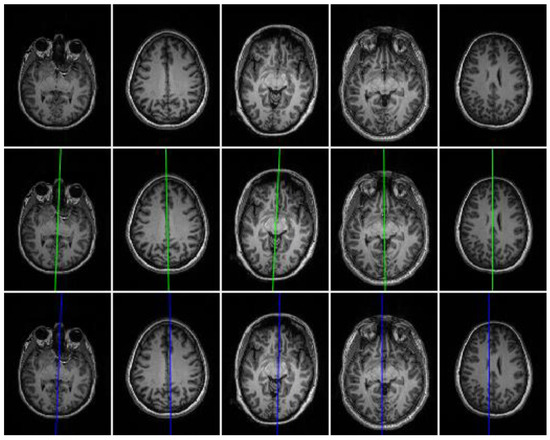

Figure 5.

Estimation of symmetry axis orientation θr. First column: input images; second column: alignment of the brain bilateral symmetry axis with the vertical axis of the image using θ1; last column: brain bilateral symmetry axis alignment using θr = θ1 + θ2. Note that θ2 = 0 in the first row.

The first row of Figure 5 indicates that bilateral symmetry axis of the brain is successfully aligned with the vertical axis (white vertical line) of the image by PCA, but sometimes as the second row in Figure 5 depicts, the bilateral symmetric axis of the brain is not completely aligned with the vertical axis of the image. Therefore, to ensure the accurate alignment of the bilateral symmetric axis of the brain with the vertical axis of the image, another fine alignment step is applied using a cross-correlation technique to find the angle θ2 with the vertical axis of the aligned image F (output of the previous step).